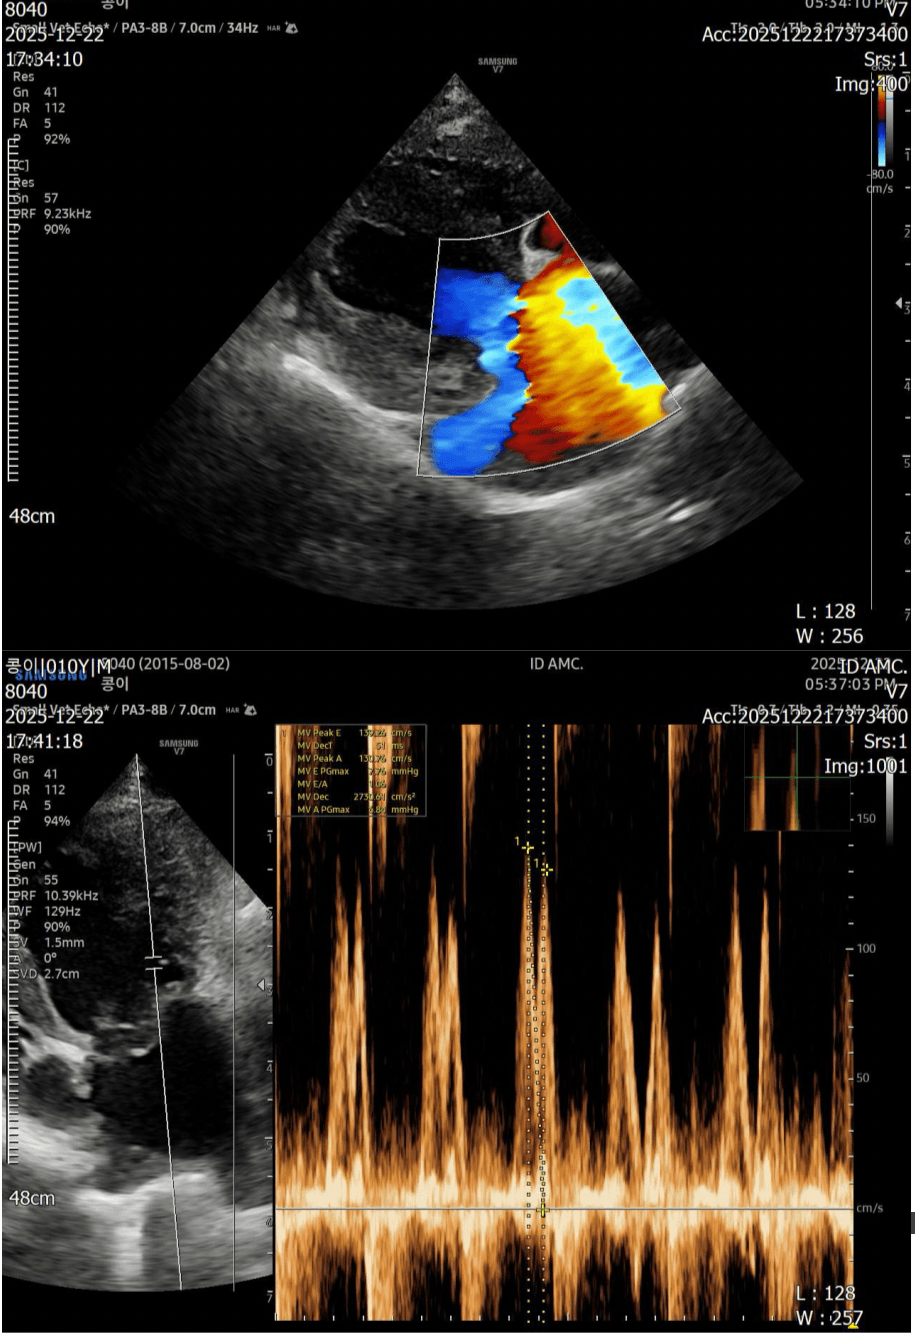

심장 판막의 이상과 비대 정도, 혈류 속도를 정밀하게 측정하는 심장 전용 초음파입니다.